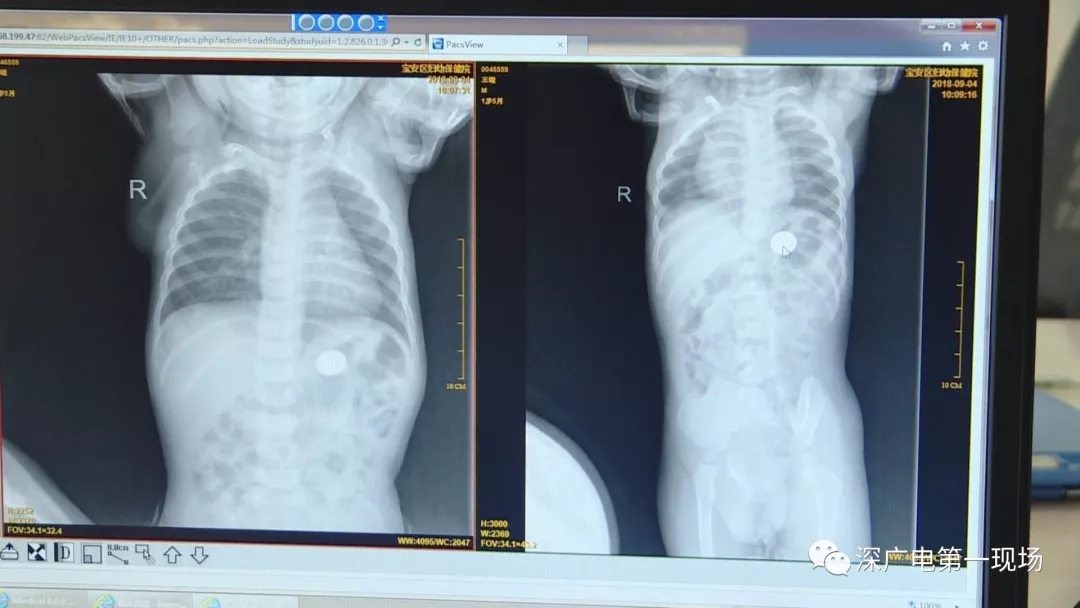

因禍得福!1歲男童摔傷送院 醫(yī)生竟從胸片中發(fā)現(xiàn)了這個…